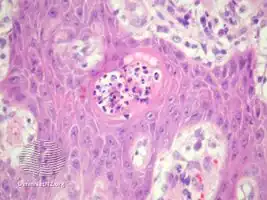

Blastomycosis-like pyoderma is a cutaneous condition characterized by large verrucous plaques with elevated borders and multiple pustules.[2]